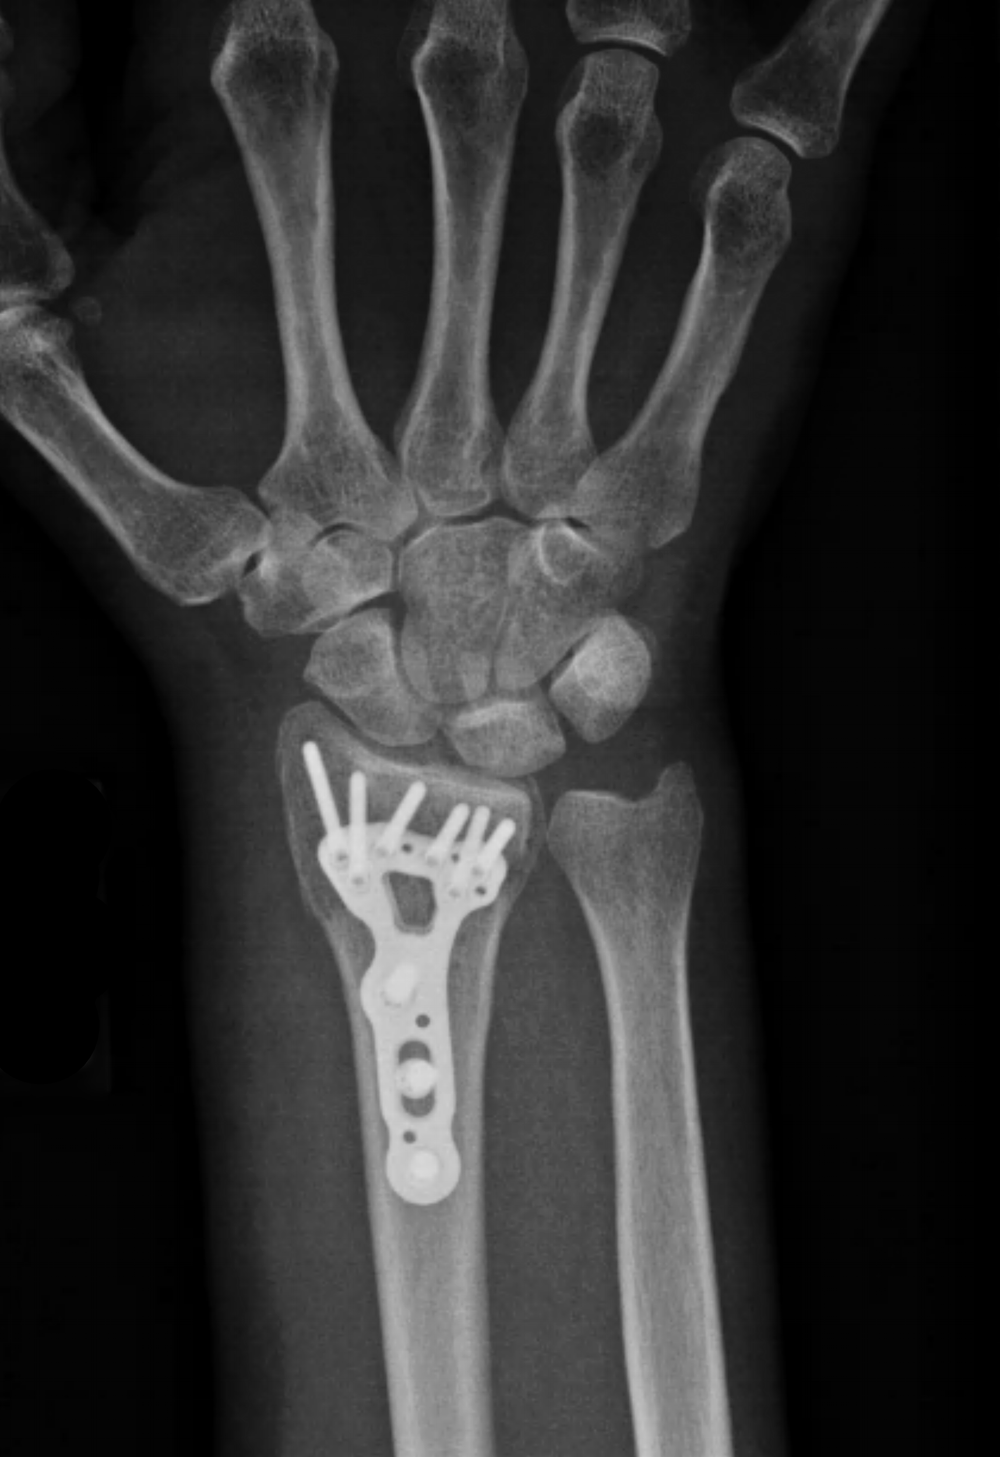

See full list on wikihow.com If the distal radius fracture is in a good position, a splint or cast is applied. Nov 13, 2019 · gently wrap the wrist in some cloth or padding to help cushion the break. Free shipping on $35 orders. What are some activities you can do with a broken wrist? Jul 08, 2011 · one option is to wrap the wrist in newspaper, magazines or bath towels and use strips of cloth to secure the ends of the splint in place; Wrist injuries are often complex and consist of fracture repair, tendon and ligament repairs, fusions, stabilizing metal implants or even joint reconstruction. Leave that task to the professionals place the splint so that it rests on the joint above and the joint below the injury. What can you do to help with a broken wrist? Doctors have developed a better way to treat carpal tunnel. Usually a cast will remain on for up to six weeks. Don't remove the splint to ice your wrist. See full list on wikihow.com

Once you've applied the splint, use a bandanna or a large piece of cloth to create a sling to hold the wrist against your chest. How long to recover from a broken wrist? If the distal radius fracture is in a good position, a splint or cast is applied. Jul 08, 2011 · one option is to wrap the wrist in newspaper, magazines or bath towels and use strips of cloth to secure the ends of the splint in place; Wrist injuries are often complex and consist of fracture repair, tendon and ligament repairs, fusions, stabilizing metal implants or even joint reconstruction.

Distal Radius Fracture Repair Includes Implants Hardware St George Surgical Center

Distal Radius Fracture Repair Includes Implants Hardware St George Surgical Center from www.stgeorgesurgical.com